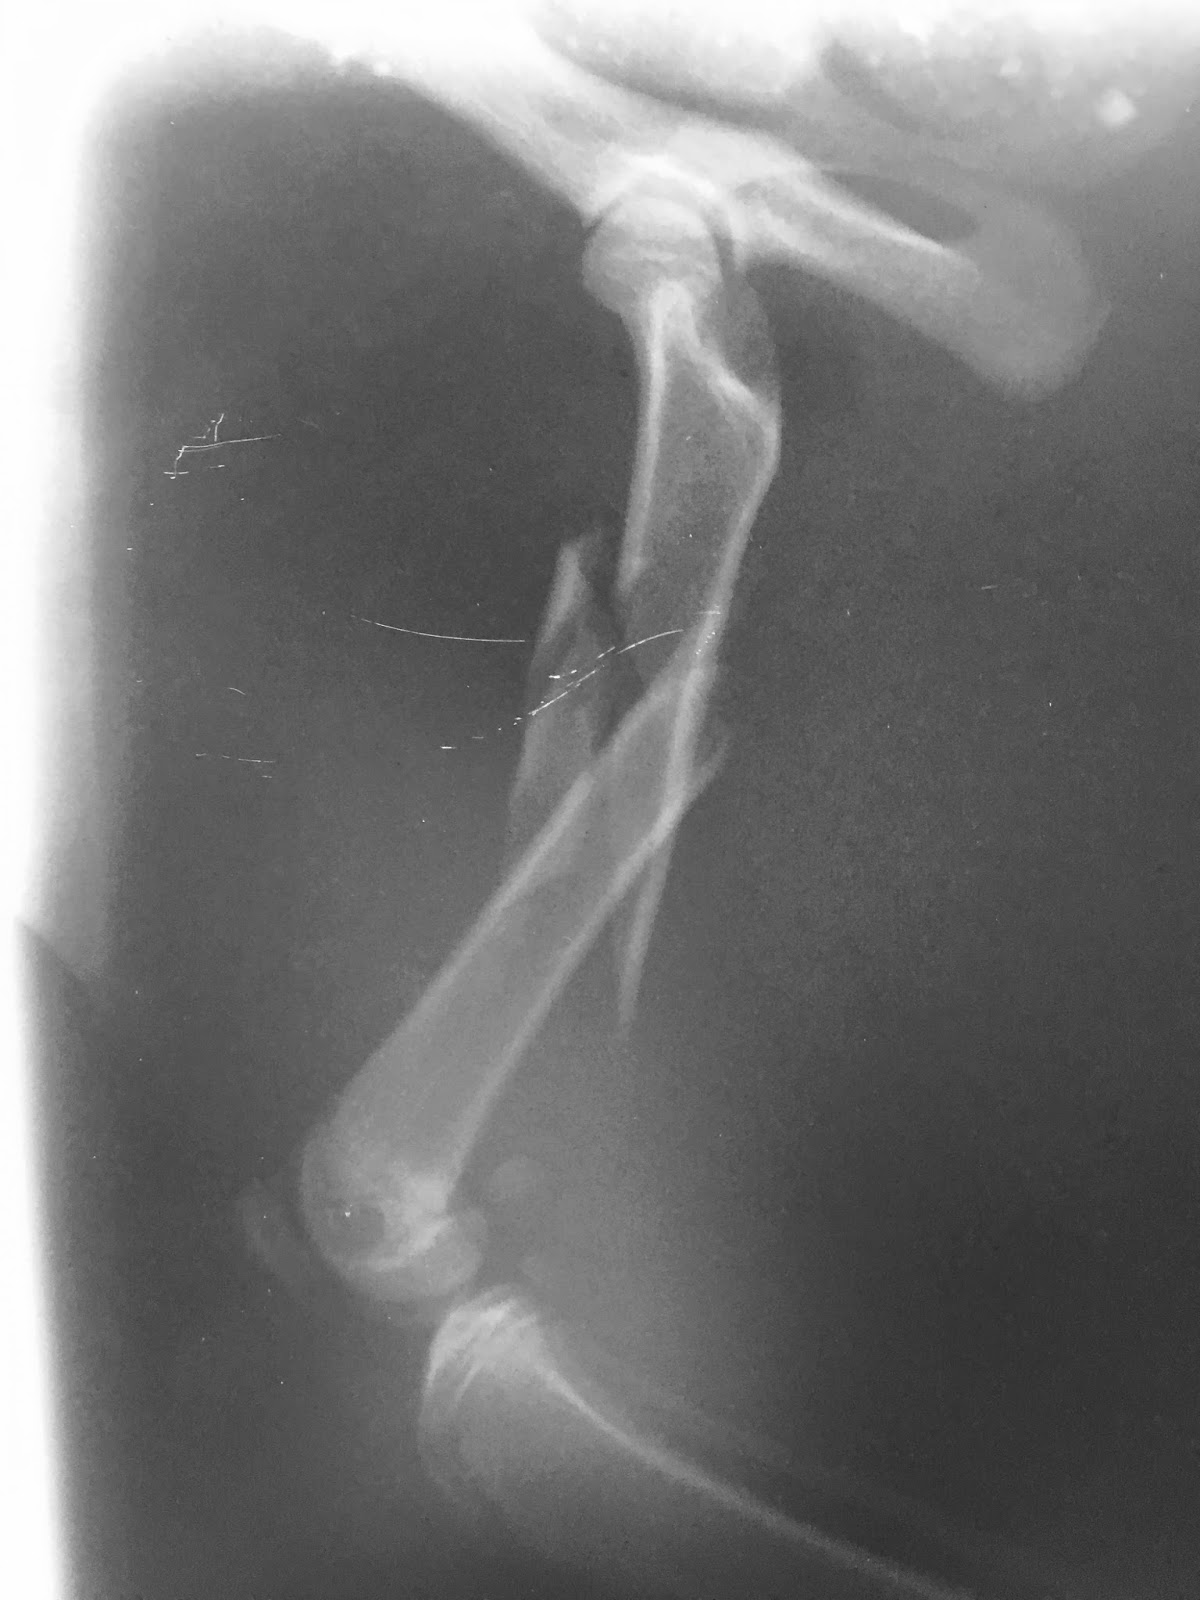

Κάταγμα μηριαίου γάτας από Πέτρος Μπεάκος13/06/201607/12/20171 σχόλιο Συντριπτικό κάταγμα διάφυσης μηριαίου οστού γάτας: οστεοσύνθεση με ήλο και σύρματα. Προσθοπίσθια ακτινογραφία Πλάγια ακτινογραφία Πλάγια ακτινογραφία μετά από οστεοσύνθεση με ήλο και σύρματα Κοινοποιήστε: Στείλε ένα σύνδεσμο σε έναν φίλο(Ανοίγει σε νέο παράθυρο) Email Εκτύπωση(Ανοίγει σε νέο παράθυρο) Εκτύπωση Mοιραστείτε στο Facebook(Ανοίγει σε νέο παράθυρο) Facebook Μοιραστείτε στο X(Ανοίγει σε νέο παράθυρο) Χ Μου αρέσει! Φόρτωση... Σχετικά